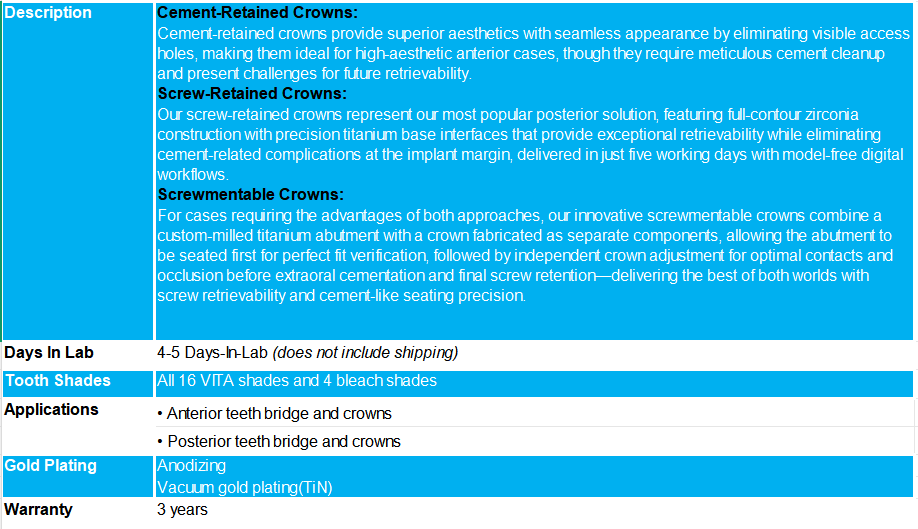

At Bluesky dental lab, we offer three distinct implant crown retention methods to address diverse clinical scenarios and patient requirements.

The choice between screw-retained and cement-retained restorations depends on specific clinical factors, including implant positioning, available restorative space, aesthetic demands, and retrievability considerations. Both retention methods have similar complication rates of 3-5%, but each has distinct advantages for different clinical scenarios.

When to Use Cement-Retained Implants

Choose cement-retained restorations when working in high-aesthetic anterior cases where implant angulation would place the screw access hole on the facial surface, creating cosmetic compromise, or when maximum esthetic demands require seamless appearance. Cement-retained cases require careful cement cleanup to prevent bacterial colonization and tissue inflammation that can jeopardize implant success.

When to Use Screw-Retained Implants

Select screw-retained restorations when implant positioning allows the access channel to exit through the cingulum anteriorly or central groove posteriorly, when restorative space is limited (requiring less space than cement-retained options), or when retrievability is important for future maintenance and repairs. Screw-retained options are advantageous in posterior applications and eliminate the risk of residual cement complications that can lead to peri-implantitis and implant failure.

When to Use Screwmentable Crowns

Choose screwmentable crowns when you need precise seating control and occlusal adjustment capabilities of cement-retained restorations while maintaining the retrievability and hygiene benefits of screw retention. This hybrid approach is ideal for complex bite relationships, challenging implant angulation, or when you need to verify perfect abutment fit before crown placement, all while avoiding intraoral cement complications and their associated risks.